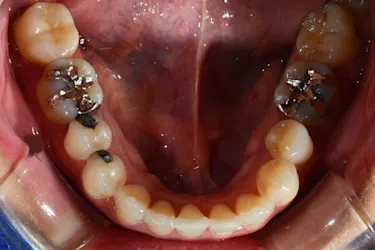

ホワイトニングも同時並行で行い、「毎週自分の歯並びの写真を撮っていたので、綺麗になっていくのが楽しみだった」という矯正体験について45歳主婦のN.T.様にお話を伺いました。

毎週自分で歯並びの写真を撮っていたので日々綺麗になっていく歯並びを見るのが嬉しく、家族からも綺麗になったねと言われました! マウスピース矯正と並行してホワイトニングも行っていたので、歯が格段に綺麗になるのを実感できたのが嬉しかったです。